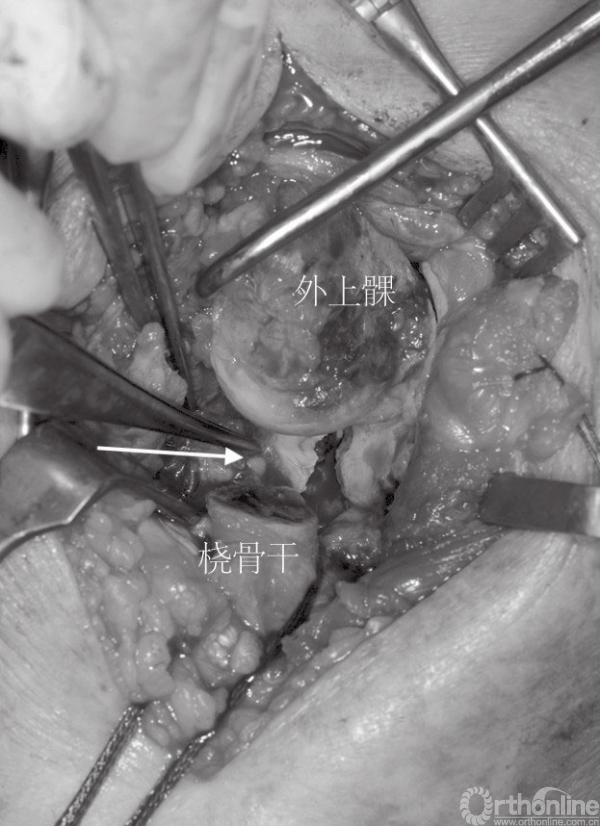

如果冠状突骨折块足够大,从外侧入路可以直接观察到,尤其是通过桡骨头的缺损处或者在桡骨头切除后。因此,在复位桡骨头之前先处理冠状突骨折,冠状突骨折块可以通过牙科刮匙进行复位和维持,然后经皮从尺骨背侧面置入空心螺钉进行固定。如果外侧入路进行固定存在困难,可以考虑直接由内侧入路进行暴露。小的游离骨折块可以去除(图4),套锁缝合前关节囊至尺骨可以加大稳定性(图5)。

图4 该损伤出现关节囊、桡侧副韧带及外侧肌肉软组织损伤(⋆桡骨头切除后)

图5 外侧入路显示冠状突骨折移位(箭头:移位的冠状突骨折部分)